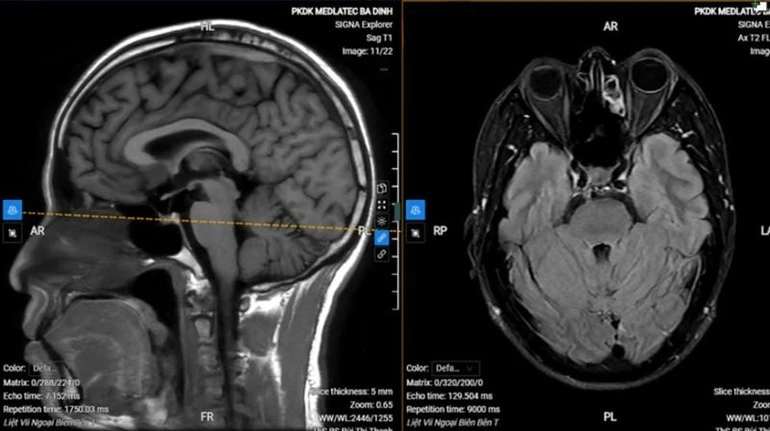

Chụp MRI sọ não cho thấy hình ảnh thoái hóa myelin chất trắng dưới vỏ bán cầu đại não bên hai bên (phân loại Fazekas độ 1), không thấy tổn thương cấp tính nội sọ.

Với kết quả trên, anh S. được chẩn đoán liệt dây thần kinh số VII ngoại biên trái vô căn (liệt Bell). Bệnh nhân được kê đơn điều trị ngoại trú, hướng dẫn tập các bài tập cơ vùng mặt, chăm sóc mắt, phối hợp châm cứu sau 1 tuần.

Hình ảnh chụp MRI của bệnh nhân.